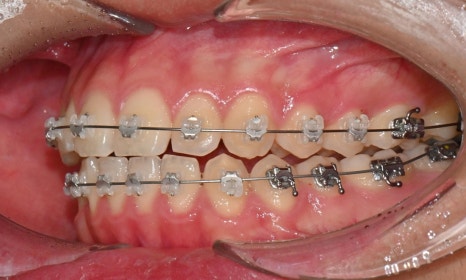

2024.12. 초진 구내사진 - 연세정원치과

정밀 검진 결과, 하악 치열이 좌측으로 틀어져 있었고 그로 인해 위아래 치아 중심선이 일치하지 않았습니다. 아래 치열이 전체적으로 전방 위치하여 아래 입술 돌출이 더 도드라져 보이는 상태였습니다. 그리고 상악궁이 하악궁보다 좁아서 앞니 부위 일부 반대로 물리는 치아 교합도 관찰되었습니다. 특히 외상 치아의 경우, 교정력 적용시 추가적인 염증성 치근 흡수 위험이 존재하기 때문에, 치료 중 지속적인 관찰이 필수적인 상황이었습니다.